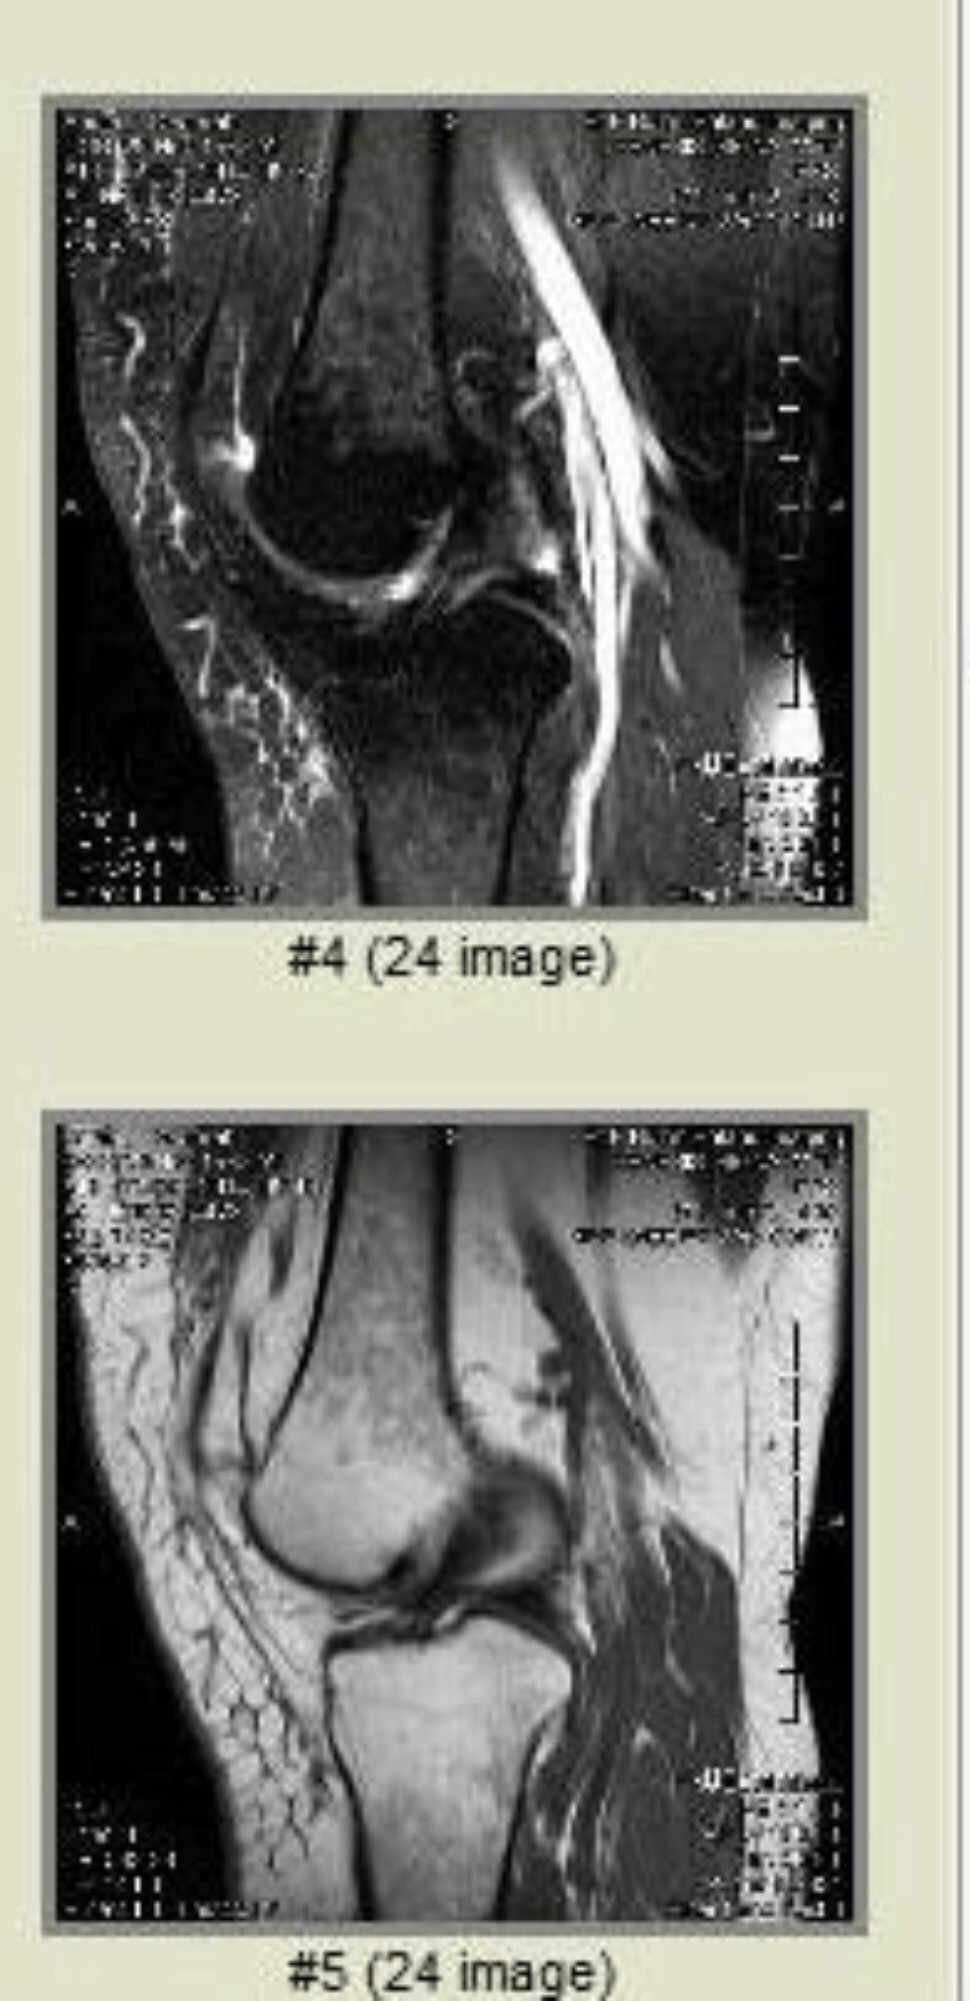

I also have Spontaneous Osteonecrosis of the Knee, also known as Ahlback’s disease is the result of vascular arterial insufficiency to the medial femoral condyle of the knee resulting in necrosis and destruction of bone. It is often unilateral and can be associated with a meniscal tear.

Osteo means Bone Necrosis means

💀

No orthopedic wants to fix it, trust me I have been to more than 5 but less than 10 for their professional opinions

The stem cell procedure is 8 to 10kusd insurance doesn’t cover any part of stem cell injections that can actually help save the bone.

All the orthopedic doctors I seen said to wait until my knee bone crumbles and collapses and then they will saw out the old bone and give me an artificial knee.